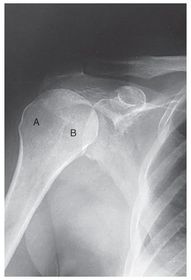

A. humeral head B. greater tubercle C. intertubercular groove (bicipital) D. lesser tubercle E. anatomic neck F. surgical neck G. humeral body